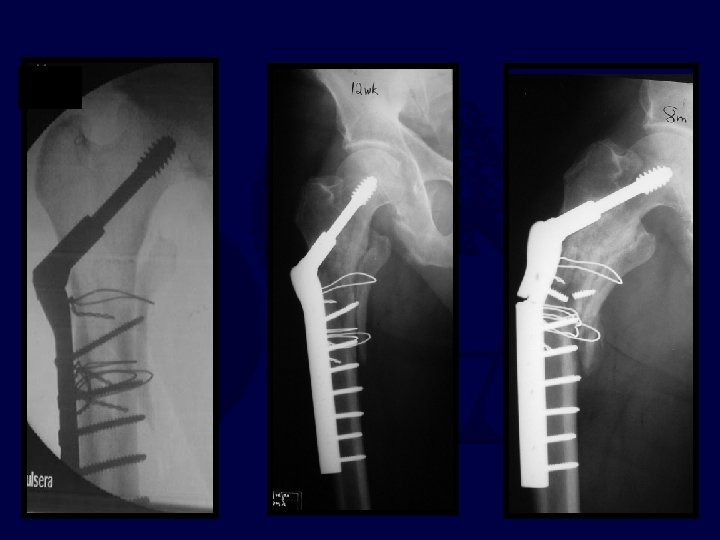

* *

Progressive pain 11 -14 weeks (varus + plate is rarely good)

I’d Bonegraft & revise with: A. 95° blade B. DCS plate C. “Recon” Nail D. DHS E. IMHS F Other

95° DCS + auto. BG